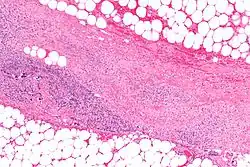

.webp.png)

Necrotizing fasciitis is ideally a clinical diagnosis based on symptoms. Due to the need for rapid surgical treatment, the time delay in performing imaging is a major concern.[15] Hence, imaging may not be needed if signs of a necrotizing infection are clear. However, due to the vague symptoms associated with the earlier stages of this disease, imaging is often useful in clarifying or confirming the diagnosis.[15]

Both CT scan and MRI are used to diagnose NF, but neither are sensitive enough to rule out necrotizing changes completely.[2]

Computed tomography (CT)

If available, computed tomography (CT) is the most convenient tool in diagnosing NF due to its speed and resolution (detects about 80% of NF cases).[16] CT scan may show fascial thickening, edema, or abscess formation.[2][15] CT is able to pick up on gas within tissues better than MRI, but it is not unusual for NF to present without gas on imaging.[15] In addition, CT is helpful in evaluating complications due to NF and finding possible sources of infections.[15] Its use may be limited in pregnant patients and patients with kidney issues.[15]

Magnetic resonance imaging (MRI)

Magnetic resonance imaging (MRI) is considered superior to computed tomography (CT) in the visualization of soft tissues and is able to detect about 93% of NF cases.[15] It is especially useful in finding fluid in the deep fascia, which can distinguish between NF and cellulitis.[15] When fluid collects in the deep fascia, or thickening or enhancement with contrast, necrotizing fasciitis should be strongly suspected. However, MRI is much slower than CT and not as widely available.[15] There may also be limitations on its use in patients with kidney problems.[15]